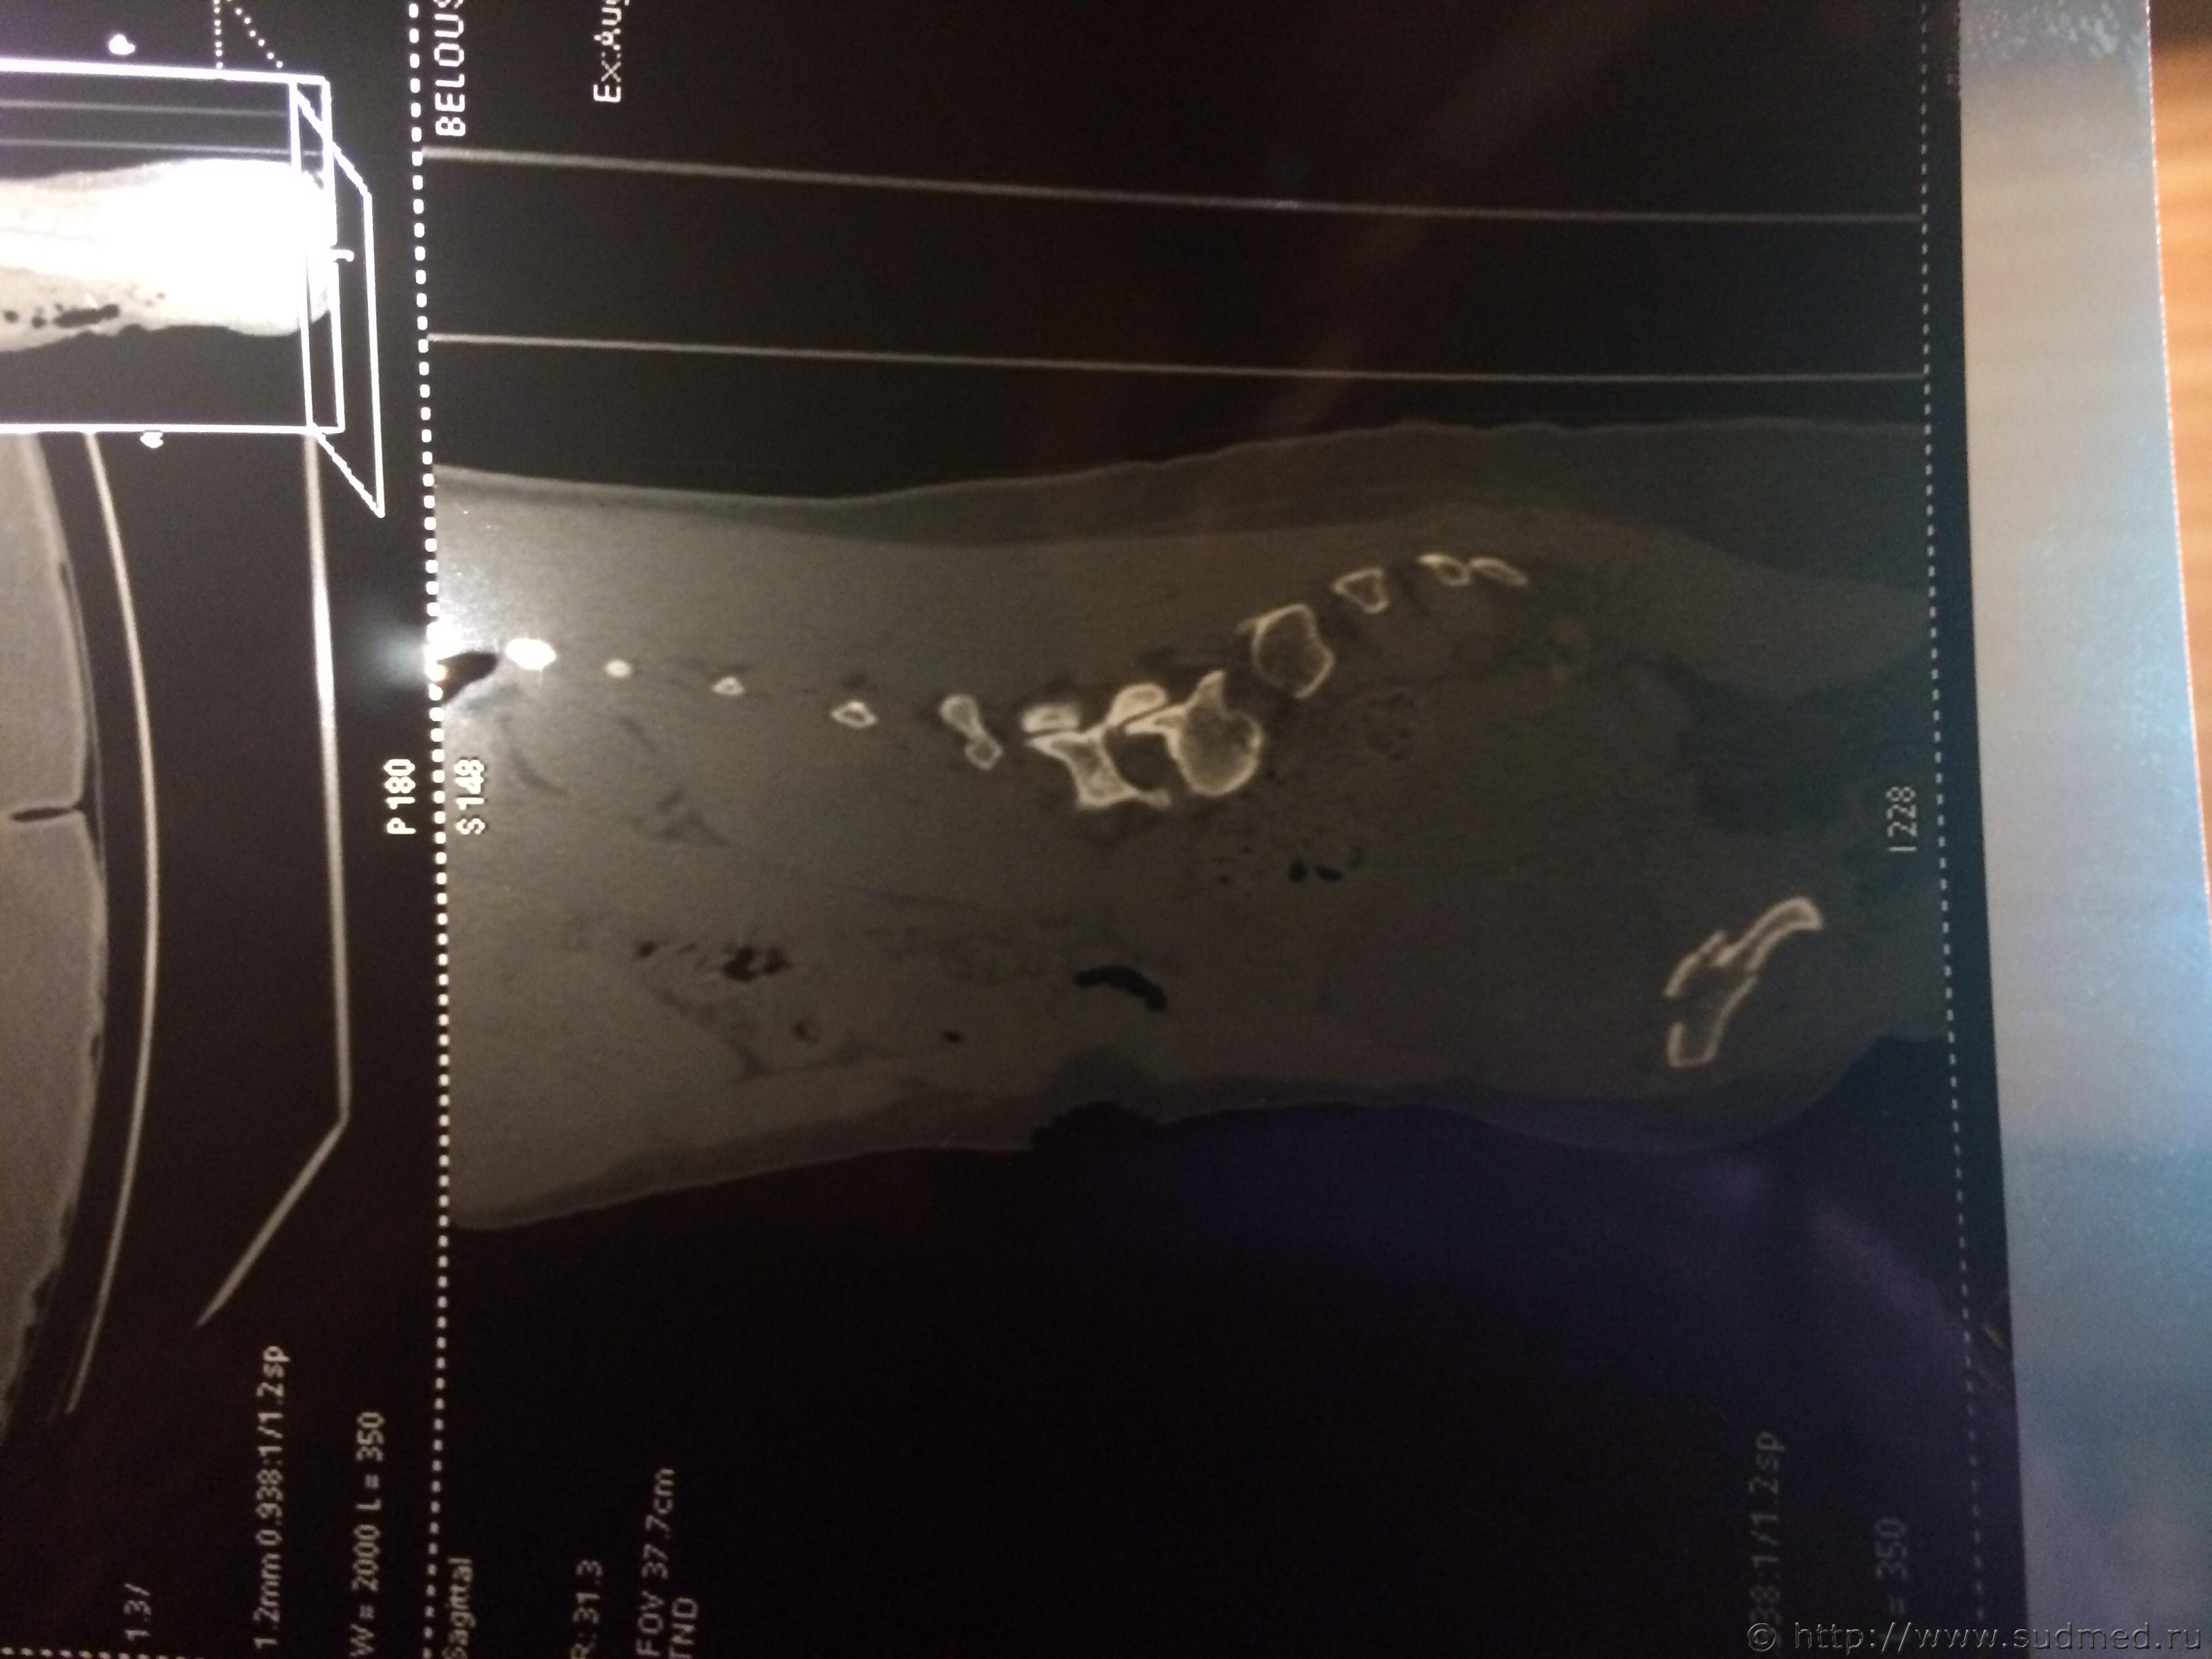

Спасибо! У меня результаты КТ, ошиблась)

КТ

Как мне видится - вертикальный перелом крестца. Тяжкий вред.

Впрочем, оставляю небольшую вероятность, что я не видел все сканы, да и качество их здесь, разумеется, хуже, чем изображение на пленке или на экране компьютера у врача, работающего на томографе.